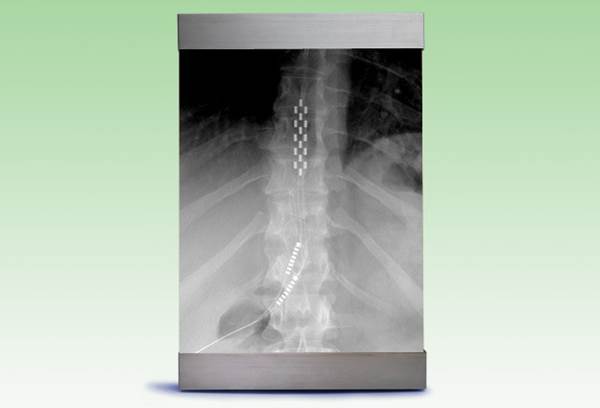

脊髓刺激(Spinal Cord Stimulation)

脊髓刺激在1967年開始變用于治療疼痛,并在1989年獲得了FDA的批準(zhǔn),用于治療軀干、手臂或腿部神經(jīng)損傷所致疼痛。脊髓刺激在治療難治性背痛綜合征和復(fù)雜區(qū)域性疼痛綜合征均有很強(qiáng)的證據(jù)支持。難治性背痛綜合征在美國是神經(jīng)刺激最常見的適應(yīng)癥。脊髓刺激同樣用于治療多種神經(jīng)痛癥狀,如心絞痛、周圍血管疾病導(dǎo)致的缺血性疼痛、枕大神經(jīng)痛、周圍神經(jīng)病變、帶狀皰疹后神經(jīng)痛,以及內(nèi)臟痛,如間質(zhì)性膀胱炎、胰腺炎和直腸病變引起的疼痛等。大量脊髓刺激的植入設(shè)備已獲得FDA批準(zhǔn),包括高精度光譜?脊髓刺激器系統(tǒng)(Boston Scientific公司,莫爾伯勒,馬薩諸塞州);protégé?MRI兼容升級(jí)植入刺激系統(tǒng)(St Jude Medical公司;圣保羅,明尼蘇達(dá)州)和Senza?(Nevro公司;紅木城,加利福尼亞州),這些設(shè)備通過提供高頻率、低振幅刺激減輕疼痛,并且不引起感覺異常。